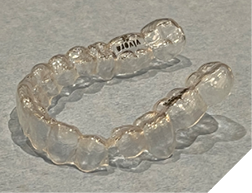

The majority of the orthodontic practices offer a period of “supervised retention” to their patients and communicates the customized retention recommendation with the patient’s general dentists. It is extremely important to work as a team to achieve long term clinical success in maintaining a functional bite and aesthetic smile. The general dentists continue to see their patients on a regular basis and have an opportunity to assess the orthodontic retainers and the bite after the supervised retention period is completed by the orthodontists. With great care, orthodontic retainers would serve for a long time (Fig. 1) without any major issues. However, in some cases, the failure to notice the clinical problems early on results in functional issues that would require a comprehensive orthodontic treatment to correct it (Fig. 2).

Fig. 1A

Fig. 1B

Fig. 1C